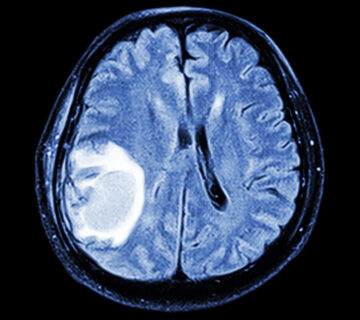

O diagnóstico da acromegalia é feito com base nos sinais e sintomas apresentados pelo paciente, além de exames de sangue para verificar os níveis do hormônio de crescimento (GH) e de outra substância, chamada IGF-1. Também é realizada uma ressonância magnética para estudo da glândula hipófise.